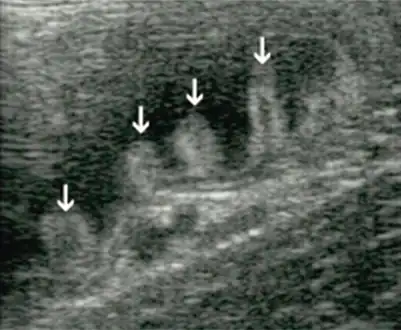

Bacterial overgrowth syndrome arrow

Aspiration of bacteria from the jejunum is the gold standard for diagnosis. A bacterial load of greater than 105 bacteria per millilitre is diagnostic for bacterial overgrowth